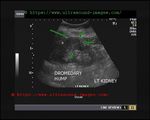

dromedary-hump-left-kidney

Dromedary hump of left kidney:

= a hump or lump bulging from the superior and lateral spect of the kidney

= always affects the left kidney and is due to the spleen compressing upon the left kidney

= name dromedary hump is derived from the hump seen in dromedary camels

= D/d: must be distinguished from renal masses. Here (dromedary humps) margins are well defined and show normal renal vessels on color Doppler ultrasound imaging

= clinically not significant; follow up will show no change in characteristics on ultrasound/ sonography